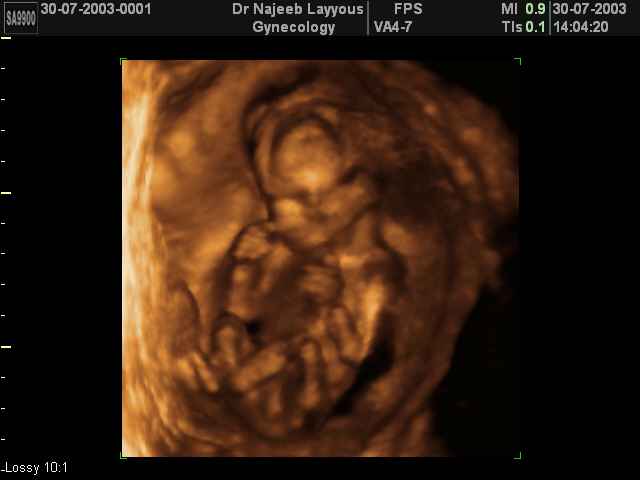

3D second trimestre échographie Photos de numérisation - deuxième partie de la grossesse | Dr N Layyous

3D second trimestre échographie Photos de numérisation - deuxième partie de la grossesse